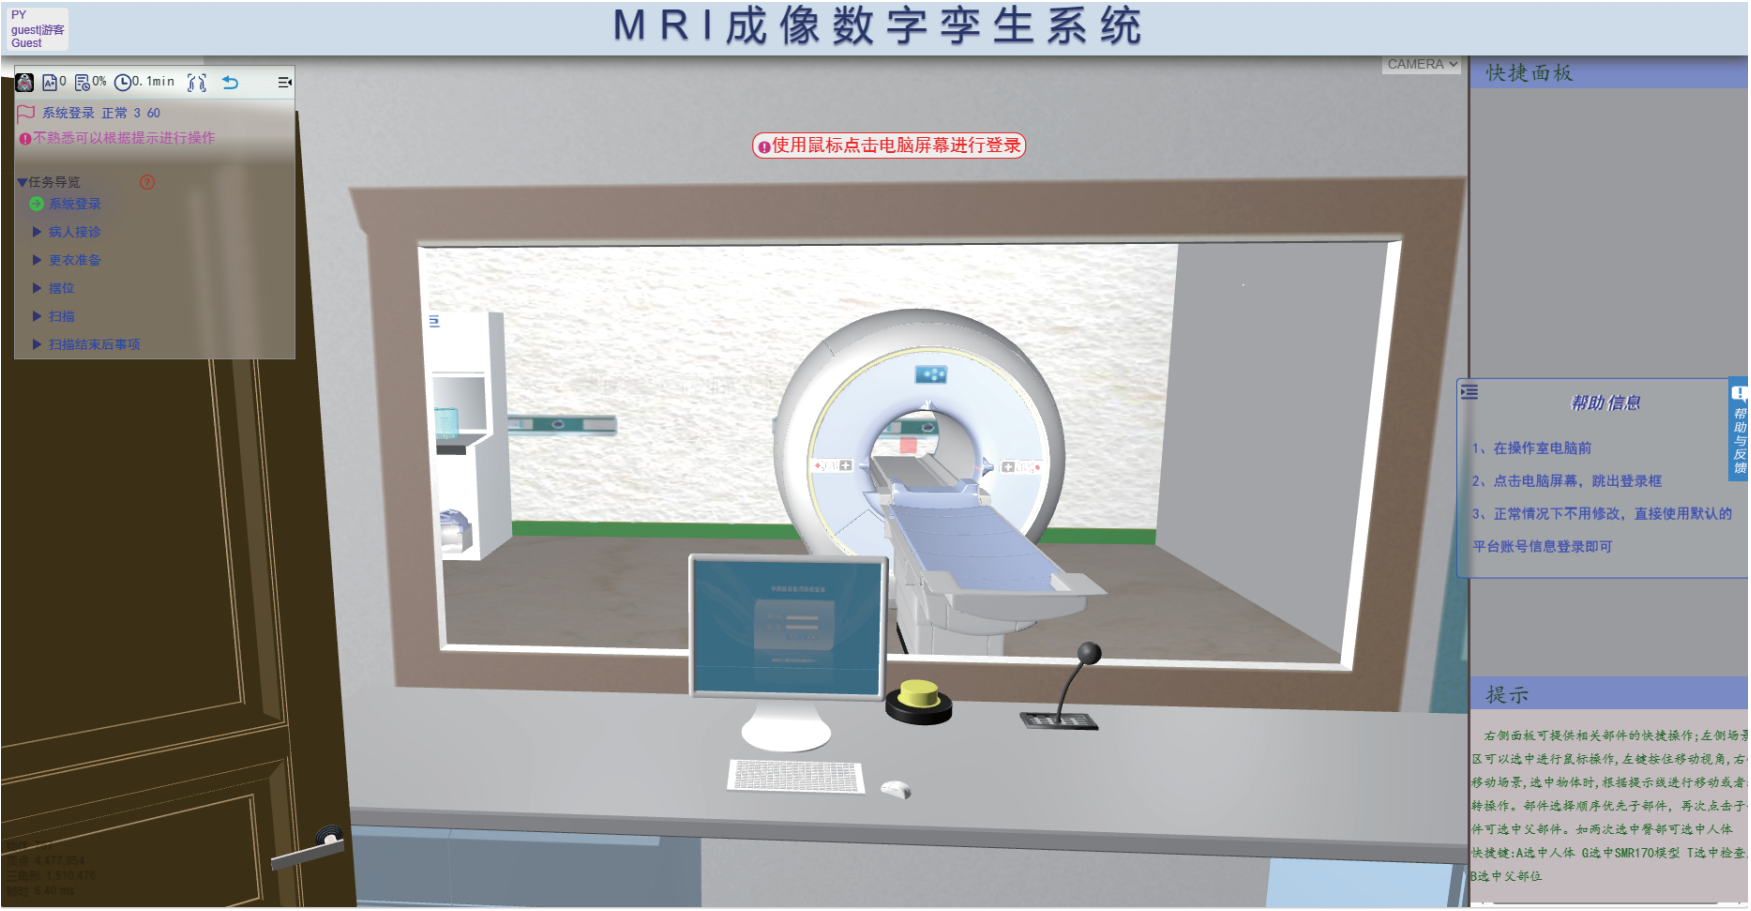

MRI成像数字孪生系统

基于数字孪生技术,研发了MRI成像数字孪生系统,模拟常见影像设备,设备操作与真实设备相同,达到使用者如同使用真实设备的效果。本场景基于真实的核磁检查流程所设计,扫描过程根据物理数字人实时计算MRI图像,包含参数可调、伪影模拟、故障诊断等各种强大功能。

基于数字孪生技术构建的 MRI 检查技术模拟系统,实现了机理与场景的深度融合,操作逻辑与真实设备完全一致,打造高度逼真的虚拟检查环境。虚拟场景完整复现 MRI 检查全流程,从技师登录、叫号、查验检查单、引导患者更衣等事项,到线圈选择、摆位、序列与参数设置等环节均细致还原。

平台界面